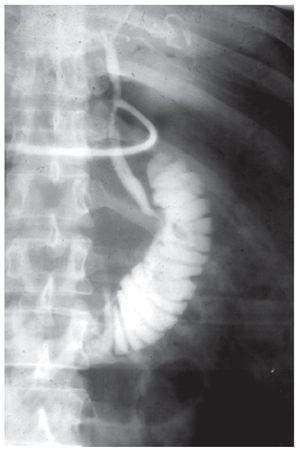

Se utilizaron para la intervención cuatro trócares colocados en espejo con respecto a la técnica que utilizamos habitualmente (uno de 10 mm y tres de 5 mm) (Figura 2). La colocación del equipo quirúrgico también fue a la inversa del modo convencional, utilizando la posición americana. Se confirmó la colecistitis aguda y se realizó colangiografía transcística encontrando tres litos en el interior del colédoco. Se intentó hacer la extracción sin éxito, por lo cual se procedió a realizar coledocotomía con extracción de los litos con catéter de Fogarty biliar, suturando el colédoco con tres puntos de Vycril 3-0 y dejando una sonda en T extraída a través del trócar subxifoideo, todo por vía laparoscópica (Figura 3).

¿ Figura 3. Colangiografía con sonda en T, donde se observa la litiasis resuelta.

El paciente no tuvo complicaciones posoperatorias; su evolución fue la habitual de la intervención mini-invasiva. Se reinstaló la vía oral al día siguiente, la ictericia disminuyó hasta su resolución total y su egreso se produjo a las 72 horas de la operación. El informe de histopatología fue 'colecistitis crónica y aguda, hemorrágica focal con peritonitis crónica leve y un ganglio cístico con hemorragia'. Su evolución fue favorable, regresando a sus actividades normales una semana después de la intervención. Un mes después de la cirugía, la sonda en T se retiró, previa colangiografía a través de la misma.